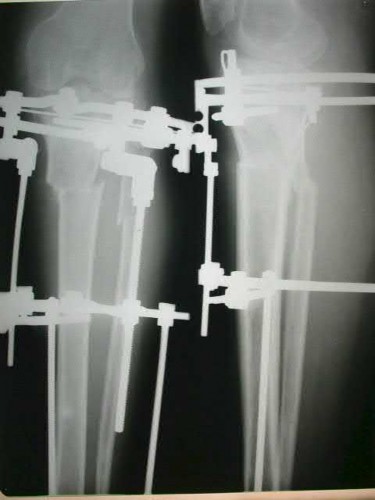

Question 3:

A 45-year-old male sustains a severe open distal femur fracture. Following debridement, a massive bone defect is treated with the induced membrane (Masquelet) technique. What is the peak time to harvest or graft the induced membrane for optimal vascular endothelial growth factor (VEGF) and bone morphogenetic protein-2 (BMP-2) expression?

Correct Answer: 4 weeks

Explanation:

The induced membrane created in the Masquelet technique possesses peak osteogenic and angiogenic properties, including maximum expression of VEGF, BMP-2, and TGF-beta, at approximately 4 weeks. Most surgeons perform the second-stage bone grafting between 4 and 6 weeks to capitalize on this biological peak.